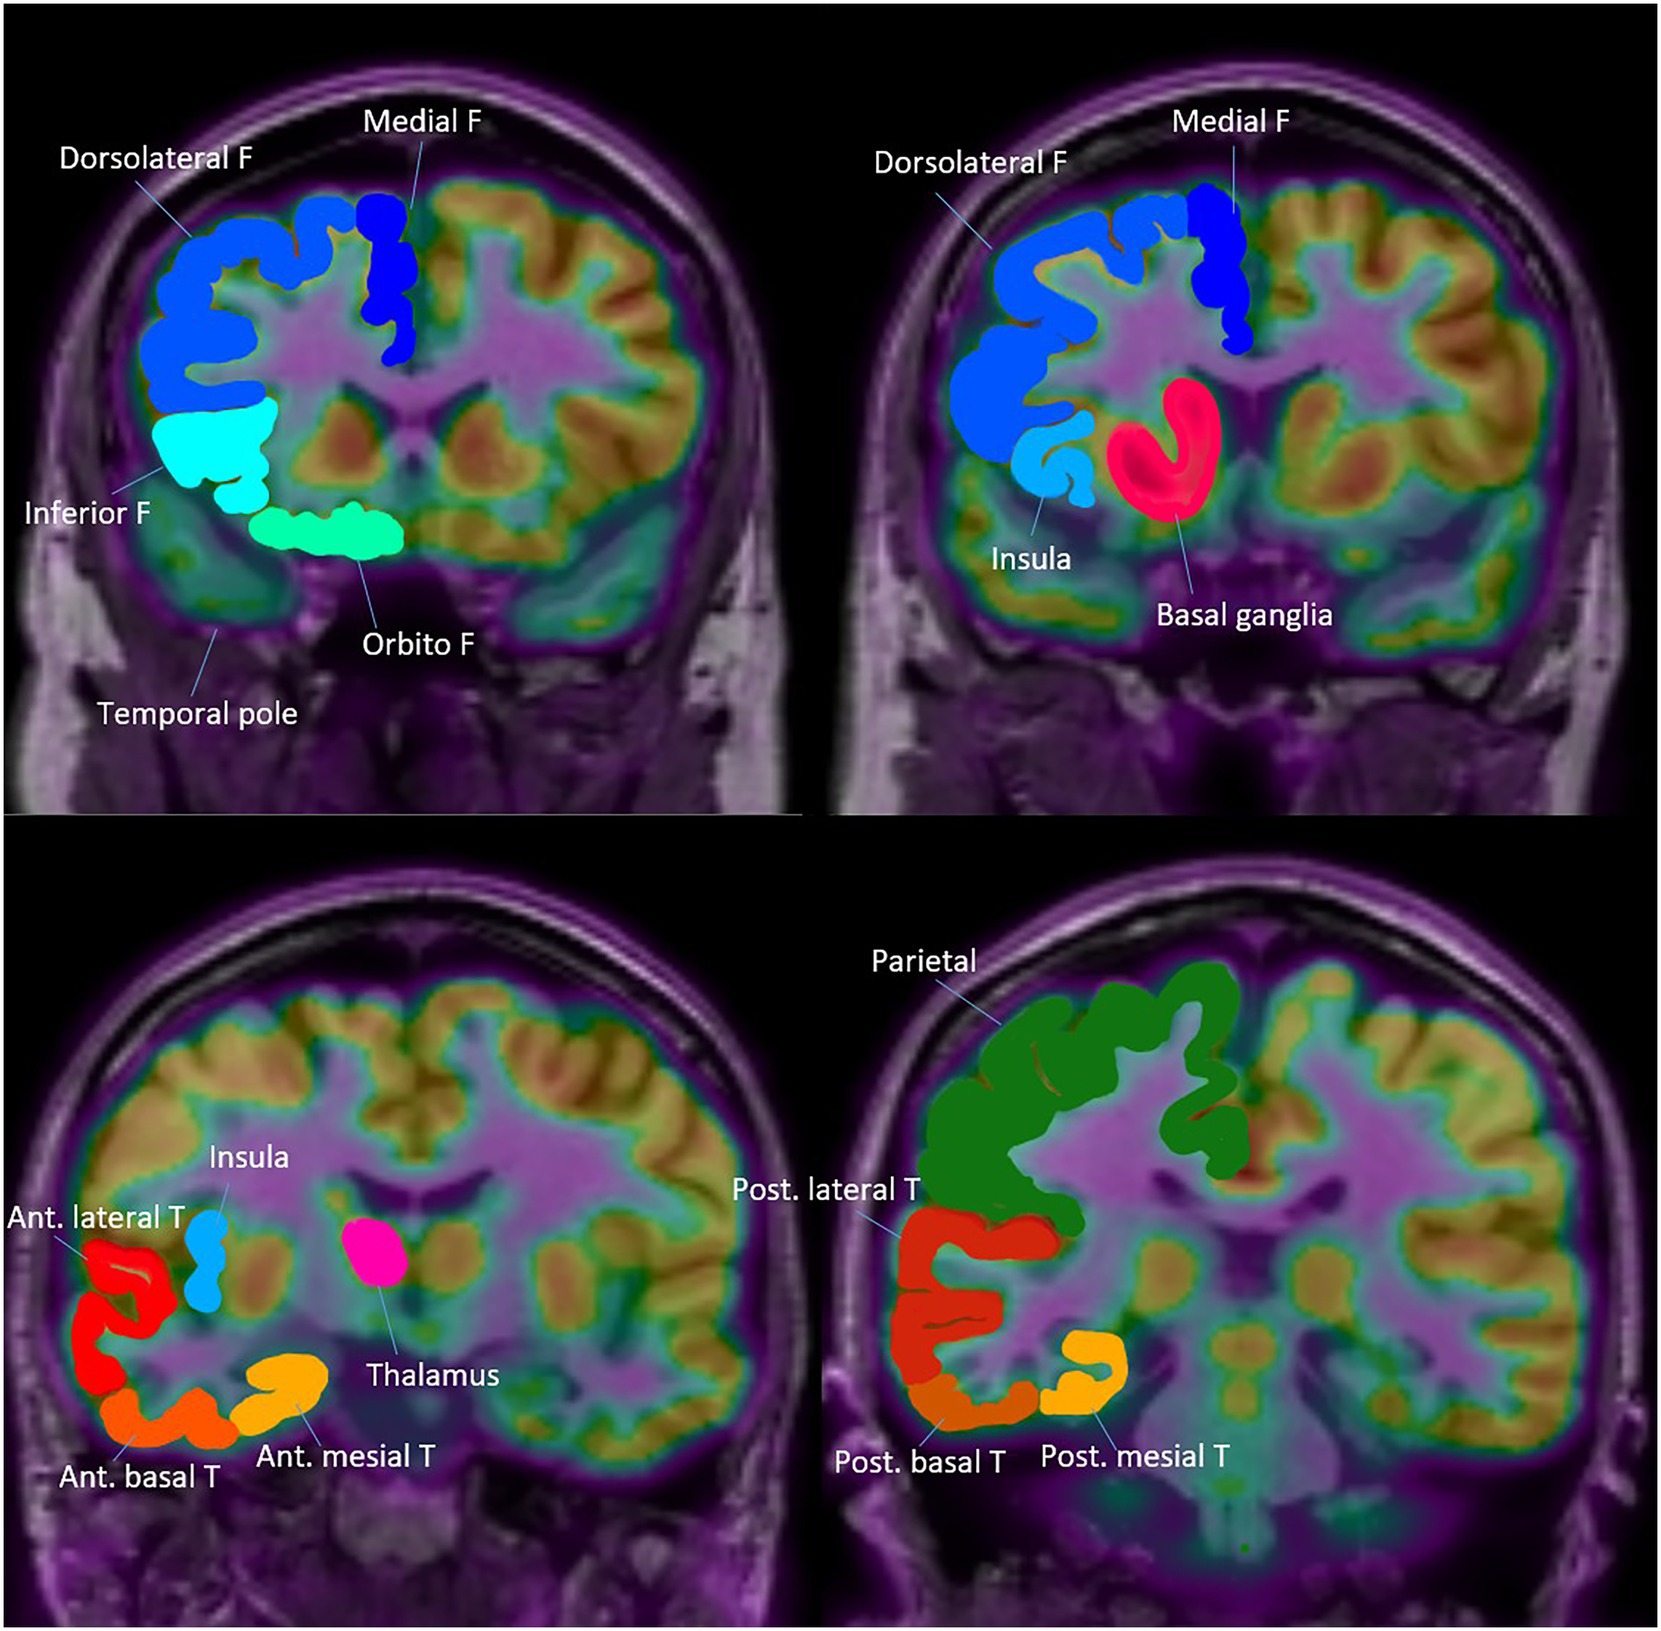

Visual analysis of PET images was conducted independently by three experienced epileptologists (H. B., Y. C., and Y. S.), who were blinded to all clinical data to minimize interpretation bias. The assessment of glucose metabolism followed a structured anatomical framework, encompassing both temporal and extratemporal regions (Figure 1). To ensure diagnostic accuracy and reliability, cases showing discordant interpretations among the three epileptologists and an additional imaging specialist underwent rigorous consensus review to establish definitive readings.

Figure 1

Topography of Anatomical areas assessed for regional hypometabolism on coronal FDG-PET images. This figure shows coronal schematic FDG-PET views outlining the anatomical areas evaluated for regional hypometabolism in the temporal lobe. It depicts anterior, posterior, mesial, lateral, and basal subregions that served as regions of interest in the analysis. The schematic provides spatial context for understanding how regional metabolism was assessed and compared across groups.

The temporal lobe was anatomically divided into anterior and posterior regions using the uncal apex as a landmark, with areas located anterior to the uncal apex classified as anterior and those posterior to it classified as posterior, in accordance with established anatomical criteria (5).